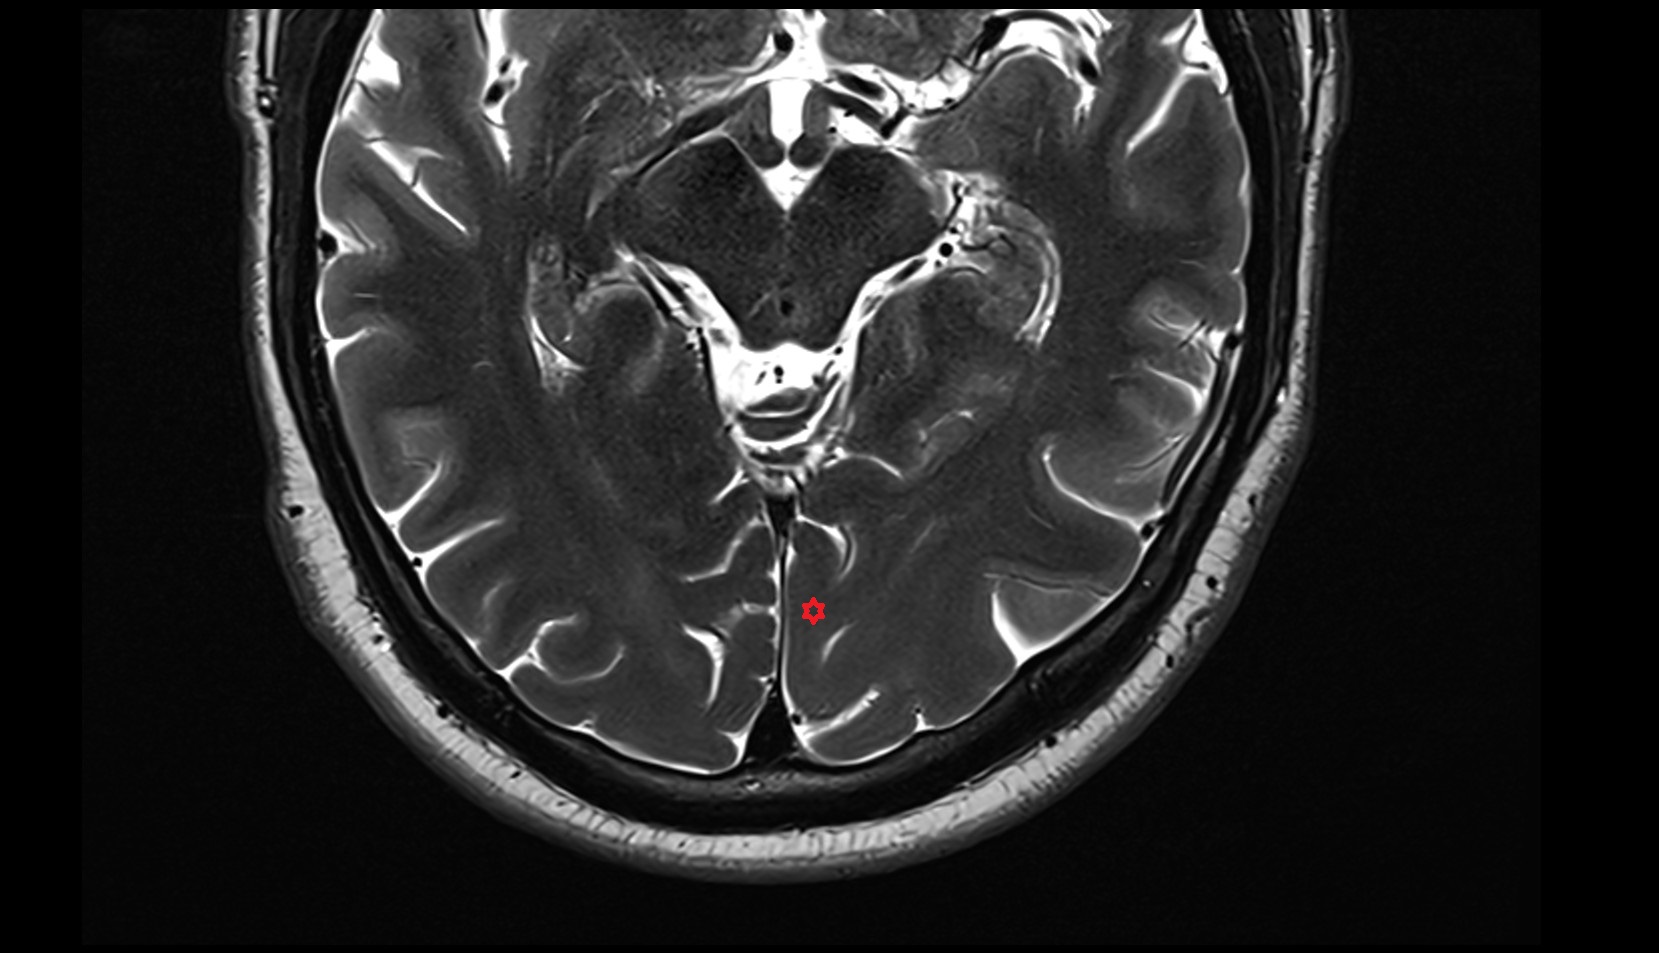

- Cerebellum